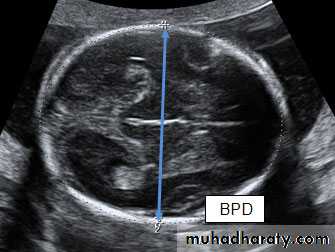

How to assess?

Fetal size can be assessed antenatally in two ways, either externally by using a tape measure to assess the uterine size from the superior edge of the pubic symphysis to the uterine fundus (symphysis–fundal height [SFH] measurement) orHow to assess?

using ultrasound to measure specific parts of the fetus and then calculating the estimated fetal weight (EFW) using equations such as those described by HadlockThe fetal size is described in terms of its size for gestational age and is presented on centile charts. Centile charts can be designed for a population